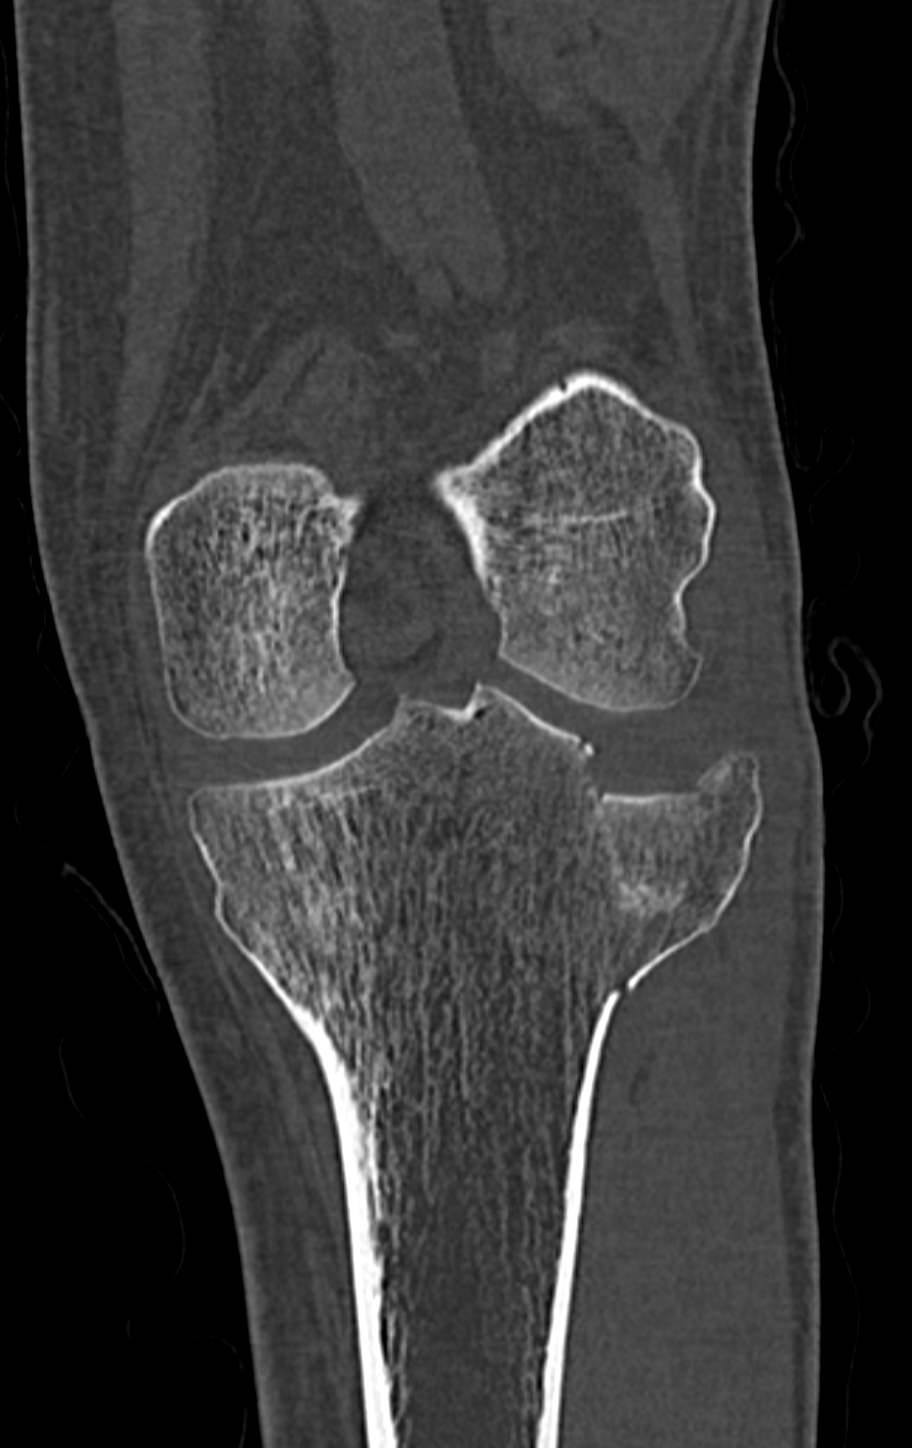

Lors d'un entraînement sur le glacier de Val Senales, l'Italienne Marta Bassino a lourdement chuté ce mercredi. Elle a été opérée dans la foulée d'une fracture du plateau tibial et sera indisponible pour une durée de 4 à 6 mois. Sa saison et ses rêves olympiques s'envolent.

Plus précisément le plateau tibial, c'est vraiment au sommet du tibia. Je me demande même si "techniquement" ça ne fait pas partie de l'articulation du genou.